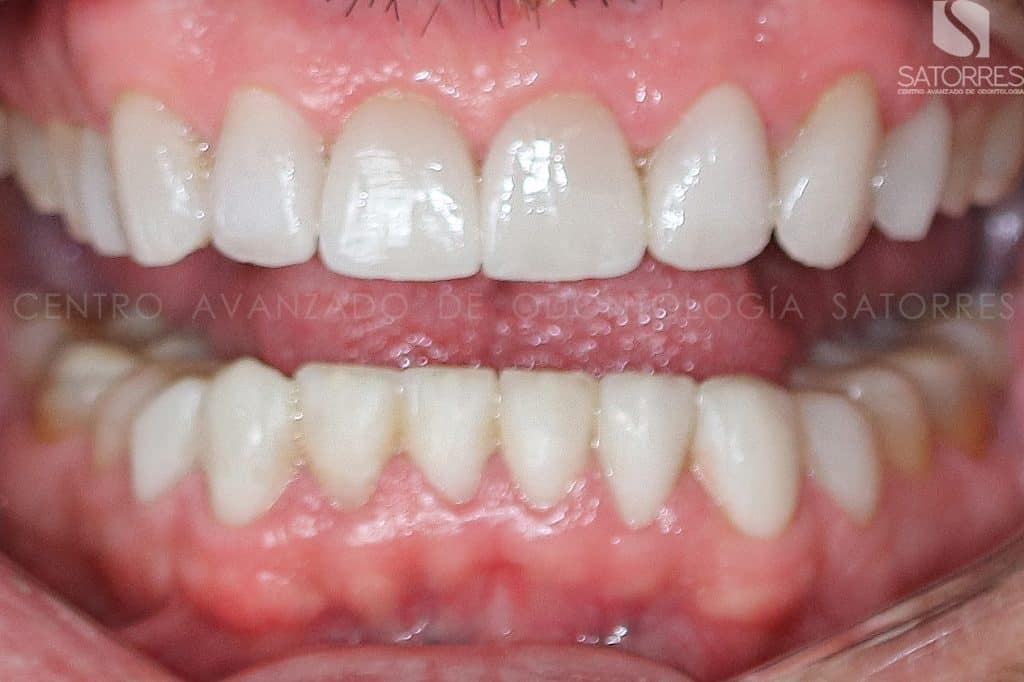

Una de las opciones más demandadas, ya que es una de las que mejor queda estéticamente y mejor resultado da, es el tratamiento realizado con carillas de porcelana.

Una vez acordado lo deseado estéticamente, se realiza el diseño final con carillas de porcelana que otorgan una gran durabilidad además de la funcionalidad y naturalidad del diente natural.

Veamos el proceso de uno de nuestros pacientes y el resultado que tuvo con este tratamiento de estética dental.